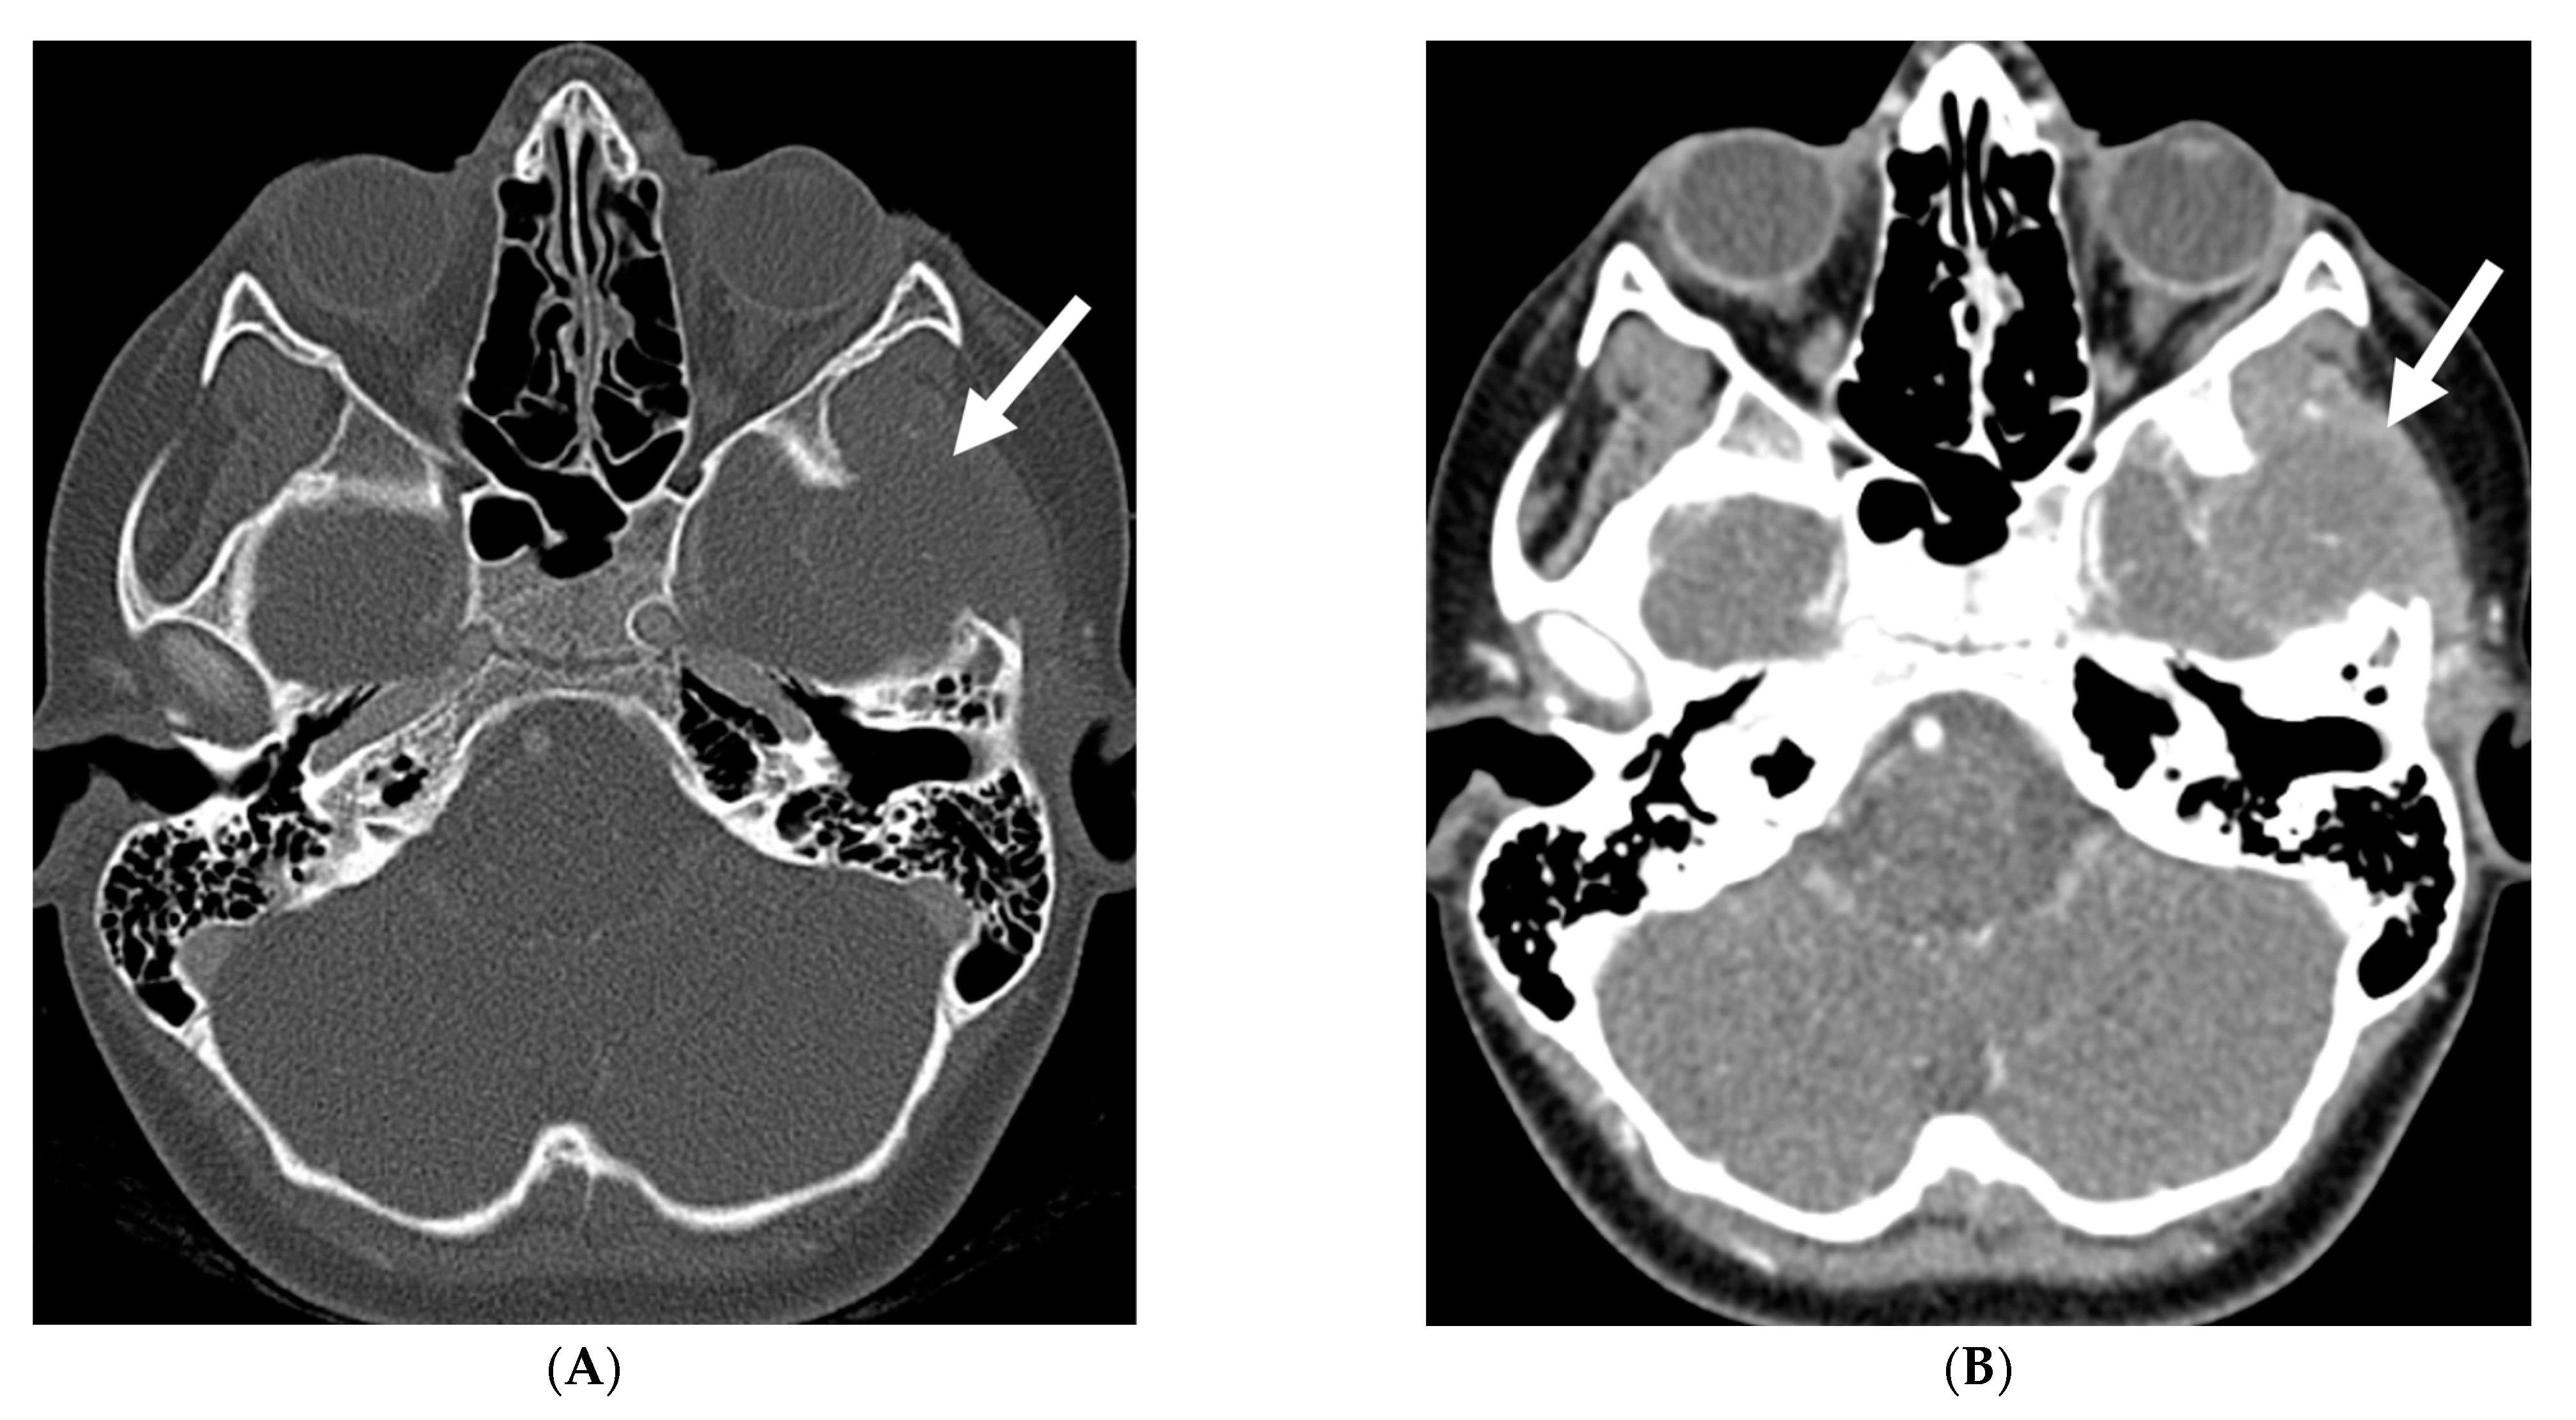

Characteristic findings on susceptibility-weighted imaging (SWI) are serpentine calcifications along the cerebral gyri [128]. While pial enhancement on postcontrast MRI is the gold standard, some patients with suspected SWS may lack this finding initially, with pial angiomatosis only becoming evident on follow-up imaging (Figure 25).

Figure 25.

Axial CT (A), Axial T2 (B) and Axial T1 post contrast (C): 12-month-old girl presented with focal left sided seizures. There is curvilinear calcification in the right temporal lobe with cortical volume loss (arrow). There is mild parenchymal volume loss and dysmyelination in the right temporal, occipital, and parietal lobes (curved arrows). Thick pial enhancement is seen in the corresponding areas (open arrows). Findings in keeping with pial angiomatosis in the right temporal, occipital, and parietal lobes. Note: Patient does not have port wine stain to support the diagnosis of Sturge-Weber syndrome.